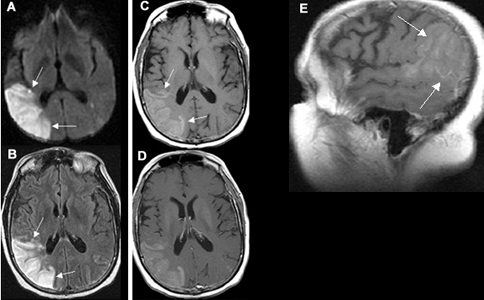

45 y/o woman with hypertension is resuscitated after a cardiac arrest. On day three she is not moving her limbs. An MRI looks like this.

There are multiple areas of watershed in the brain

MCA is most affected in global hypotension

Posterior circulation is rarer

A 20 year old man tries to commit suicide by hanging himself. He is cut down after several minutes and is pulseless. He is resuscitated and regains a heartbeat and respiratory drive and cough to suctioning. Three days later, his exam has not changed.

Where is the lesion?

cortical lamniar necrosis